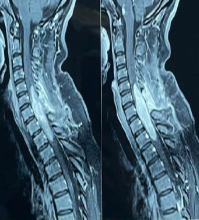

Acute post-surgical pneumocephalus is frequent in patients with cranioencephalic pathology operated on in the supine and prone position. The distribution and degrees of pneumocephalus may be related to sex, the type of cranioencephalic pathology, and the depth of the surgical lesion.